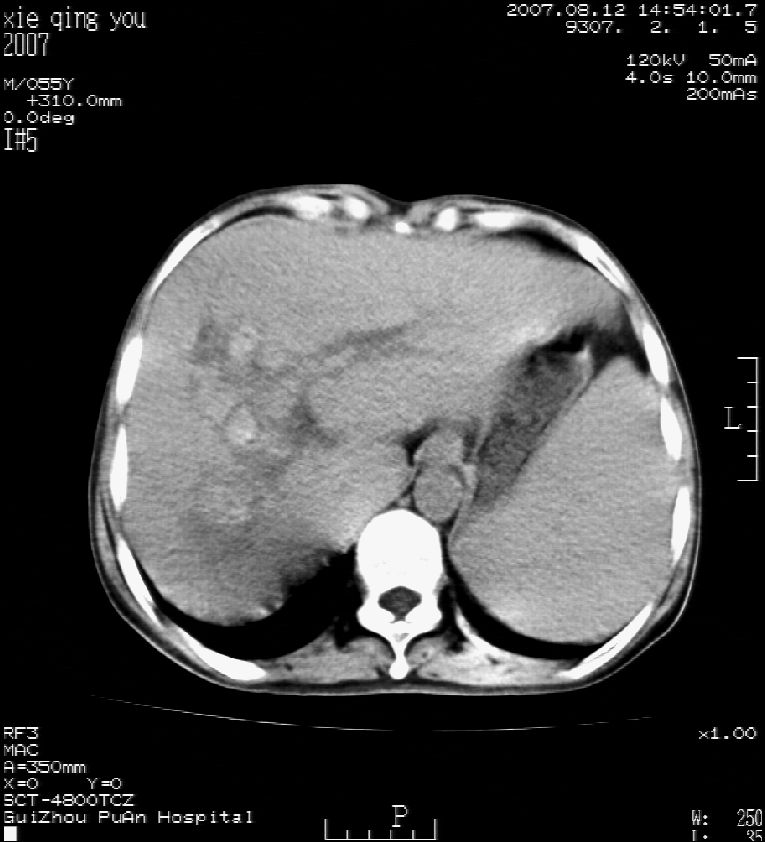

2007年8月片

这个病灶很有意思,怎么可能没有了呢?我考虑当时很可能是肝脏脓肿(b超示囊肿是有可能误诊的,因为影像表现都是低回声吗?),现在脓肿吸收了,肝脏萎缩,肝裂增宽了.别的肝叶代偿增大,不过现在左内叶的确有个占位,肝内多发结石,脾脏比以前大,不排除有肝硬化可能.建议增强扫描给于定性!!!!

肝硬化\\脾大,肝左叶肝癌可能性大,建议增强扫描.肝内胆管多发性结石.

肝内胆管多发性结石;肝硬化脾肿大;肝左叶肝癌可能性大,建议增强。